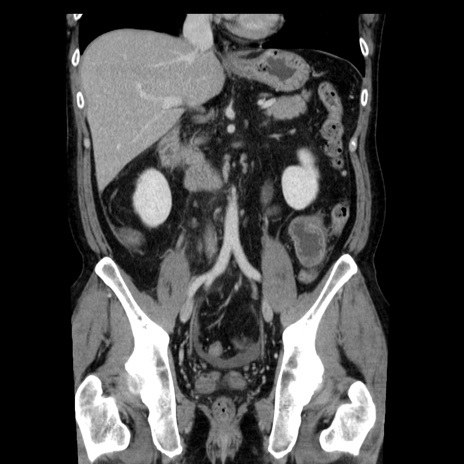

症例29(冠状断像)

【症例】40歳代男性

【現病歴】2日前から胃痛あり。徐々に周期的な激痛に変化した。本日になっても激痛があるため受診。

【身体所見】意識清明、BT 38-39℃台あり、腹部:膨満、やや硬、右下腹部に圧痛あり。

【データ】WBC 8500、CRP 23.26